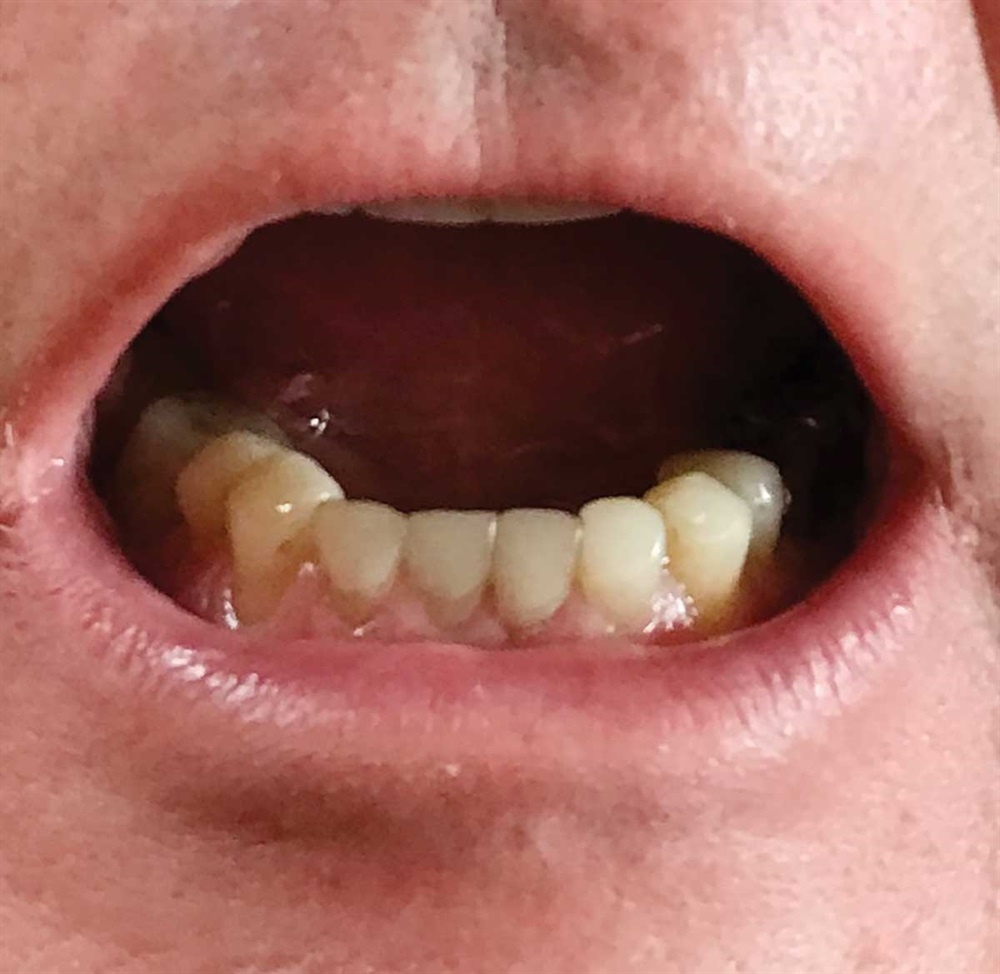

Fig. 1: June 2018. Where did all the tooth structure go? Grinding in protrusion? There is serious wear and tear. This 63-year-old gentleman has been wearing out his teeth, especially in the past 10 years.

Show Your Work